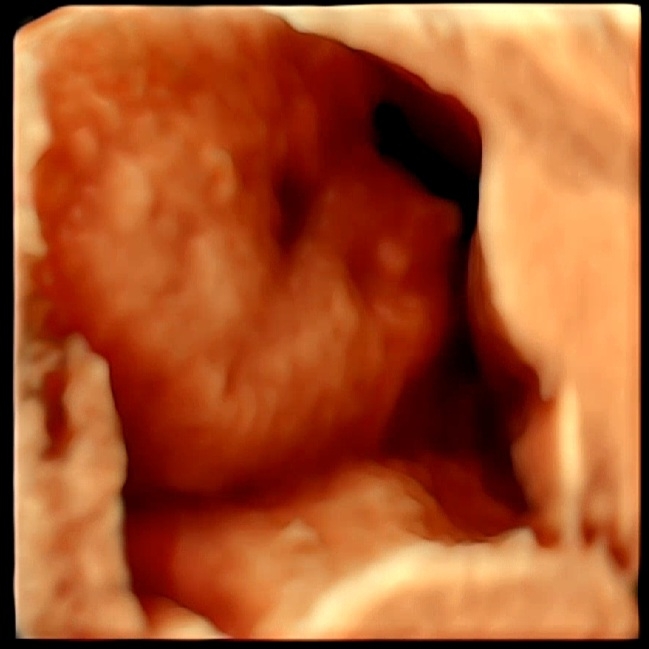

심실중격결손

어제 25주차 정기검진하규.. 임당테스트했어요! 단백뇨가 아주 약하게있었어서 ㅜ 혹시 임신중독증인가싶어서 ㅠ 임신중독의 증상중 하나인 공포의 임당검사를 엄청 걱정했는데... 다행히 임당은 무사 통과! 기분 좋게 정밀 춈파 검사했는데 ㅜㅜ심장쪽을 엄청 오래보시능거애요..ㅜㅜㅜㅜㅜ 불안함의 시작.... 아니나 다를까.. 산부인과 의사샘이 "심실중격결손"이라고.. 심장에 아주작은 구멍이 보인다구...ㅠㅠㅠㅠ 얘기듣자마자 심장이 철렁하고.. 눈물이😭😭😭😭 대학병원 가보라는 소견내주셔서 예약하구..ㅜㅜ 혹시 베동중에서도 아가 심실중격결손 진단? 받으신분 계신가요..? ㅜㅜ 흔하다고하는데 너무 걱정이되어요 ㅜㅜ